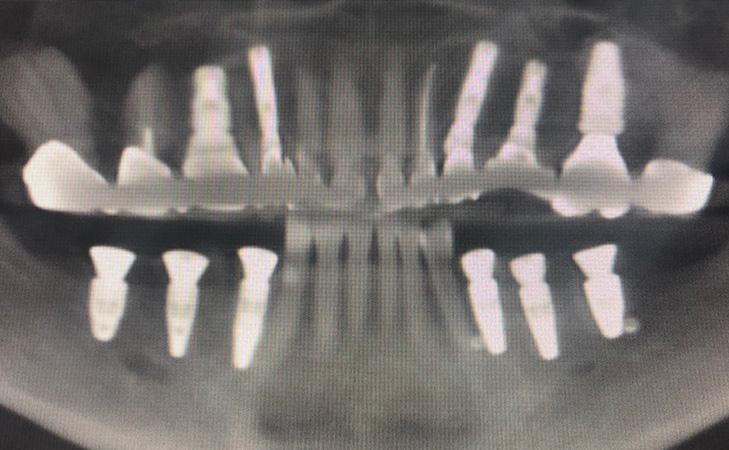

This 74 year old patient was unhappy with her current smile and the existing teeth were unsalvageable. Utilizing computer planning and guided implant placement, the teeth were extracted and implants were placed on the same day. 6 months later, final bridges were made and the patient was thrilled with her new smile.

Patient had a 3 unit bridge that was decayed. A CT scan was taken to evaluate the surrounding bone. Patient underwent extraction and Bone Grafting to regenerate and build the necessary bone for implant placement. Implant was placed. Final x-ray showing 3 implants placed to replace the bridge.

Patient has been missing lower left teeth for years. Developed large ridge defect from not having teeth. Pre surgical CT scan shows thin ridge with inadequate bone volume to place implants. Ridge bone graft was done. Special covering placed and secured. CT scan after 4 months of healing. Final post implant placement x-ray.

This is a 70 year old male who was unhappy with the fit of his lower denture. I placed 4 dental implants to anchor the denture and the patient was very comfortable.

This patient presents missing right and left lower jaw teeth. Jaw bone was regenerated using the latest techniques and 3 dental implants were placed on each side for permanent crowns.